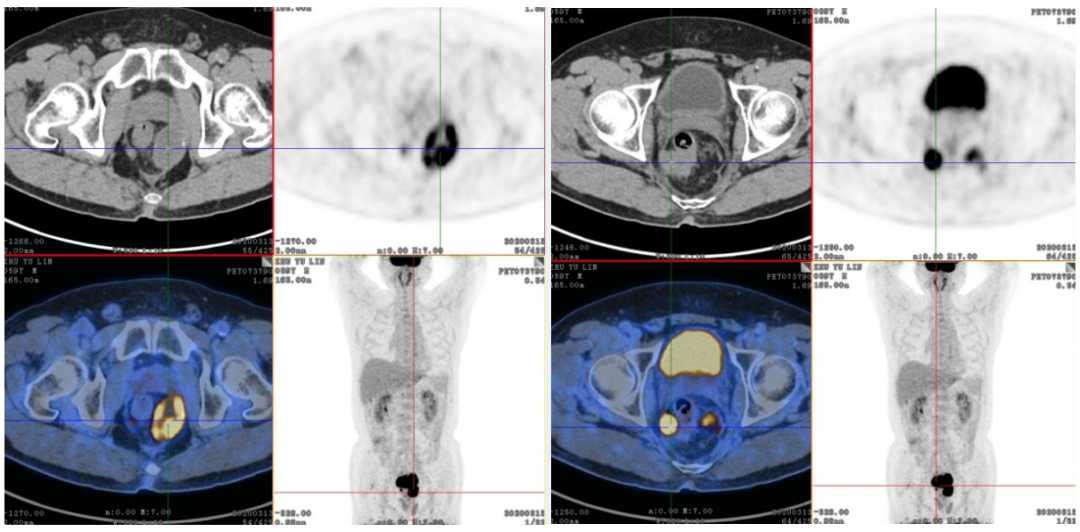

2020年3月16日,行PET-CT检查: 直肠中下段肿瘤复发(SUVmax=20.1)伴双侧盆底部多发淋巴结转移可能性大(较大者约4.8*3.1cm,SUVmax=10.7-15.1)。疗效评估为肿瘤进展(PD)。

2020年4月10日至2020年10月10日,给予二线第1-10周期FOLFIRI方案化疗联合贝伐珠单抗靶向治疗,2020年6月26日,9月7日,两次疗效评估为SD。